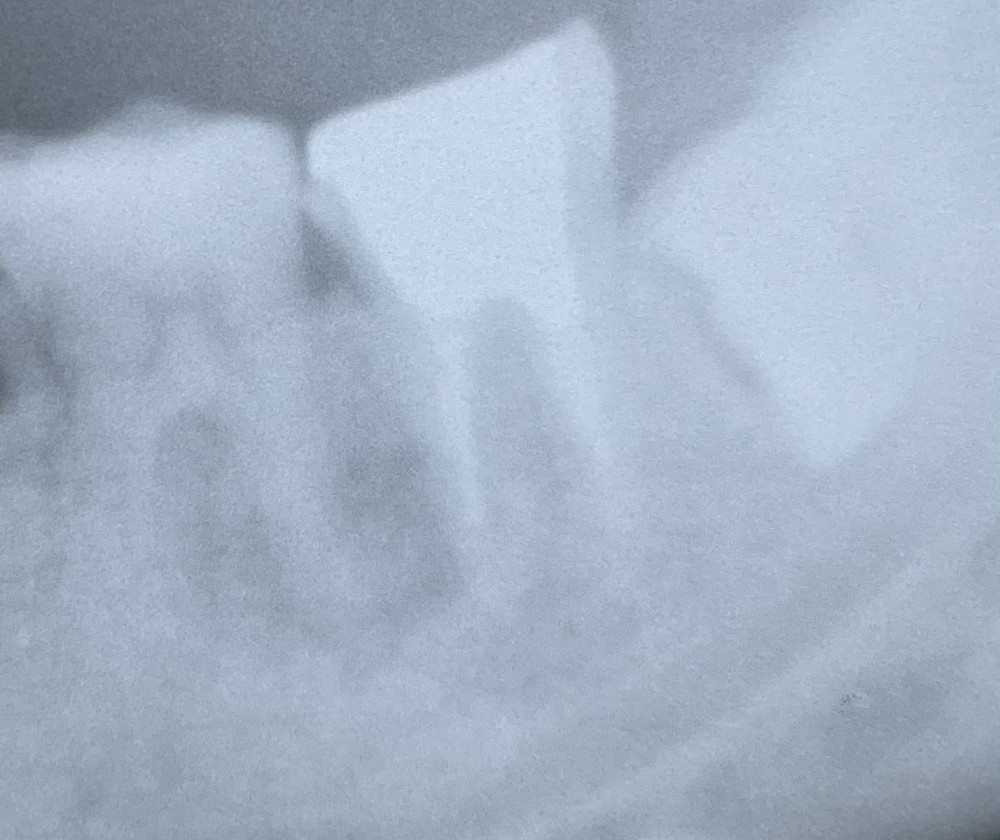

こちらのエックス線写真は、ある20代後半の患者さまのものです。

令和4年4月初診。左下奥歯の歯茎の腫れと痛みを伴い、当院に来院されました。

左下奥歯の下顎骨の部分のエックス線写真です。

楕円形に見える黒い部分に病巣が写っています。

病巣は2本の奥歯にまたがっているため、

病巣の原因となった歯を特定するのが困難な状況です。